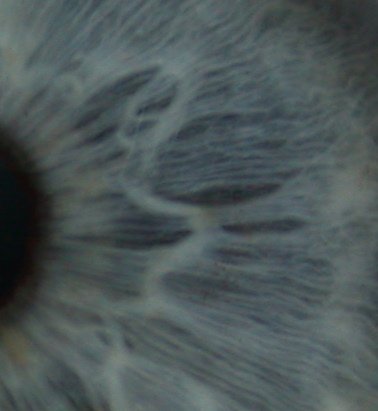

The diagram above is an example chart of the areas of the iris of the right eye (a mirror image chart relevant if you are looking in a mirror). There is a lot of close up detail contained within the iris including possible fibre anomalies, pigments, whitening and shape variations of the structures it contains. Sclerology is a similar study of the blood vessels, colours and patches of the whites of the eyes which adds more information to that obtained from iridology.